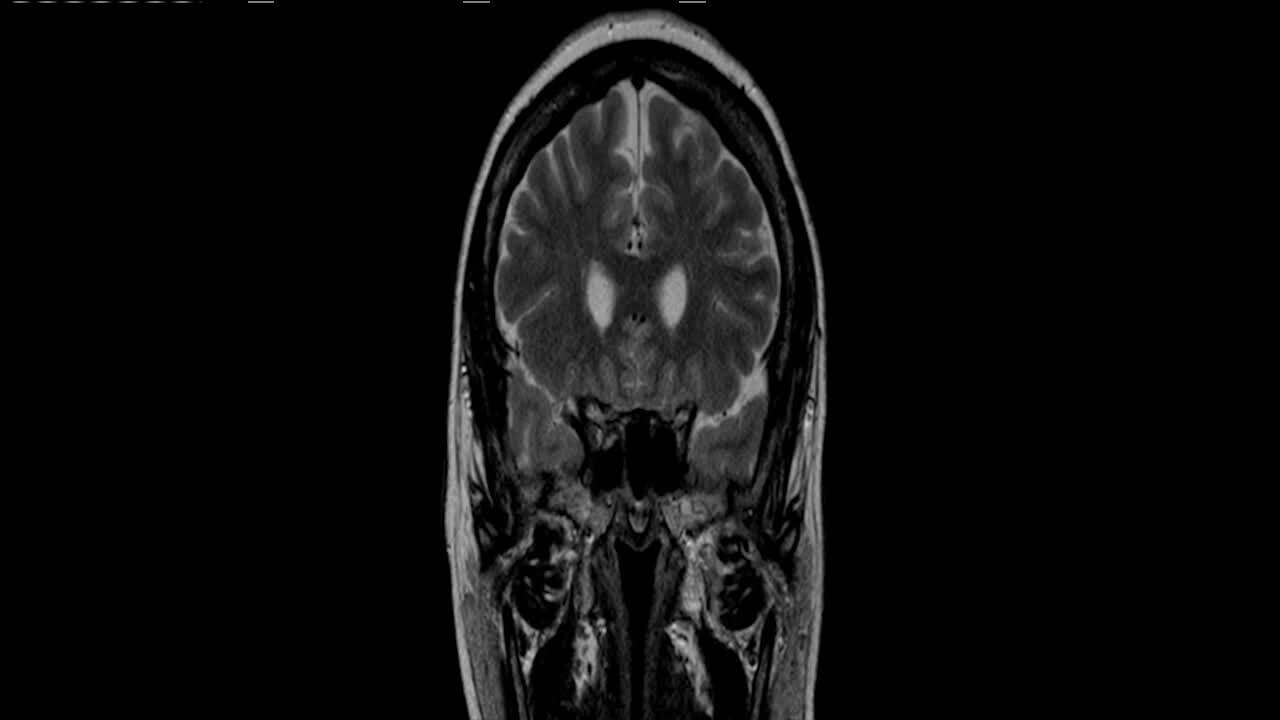

When it comes to surgery, Medtronic has just created a process of deep brain stimulation that can counteract tremors in real time without waiting for medication to kick in. It’s called Percept. But it’s still not a cure.